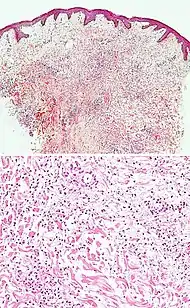

Spongiotic dermatitis

It is characterized by epithelial intercellular edema.[2]